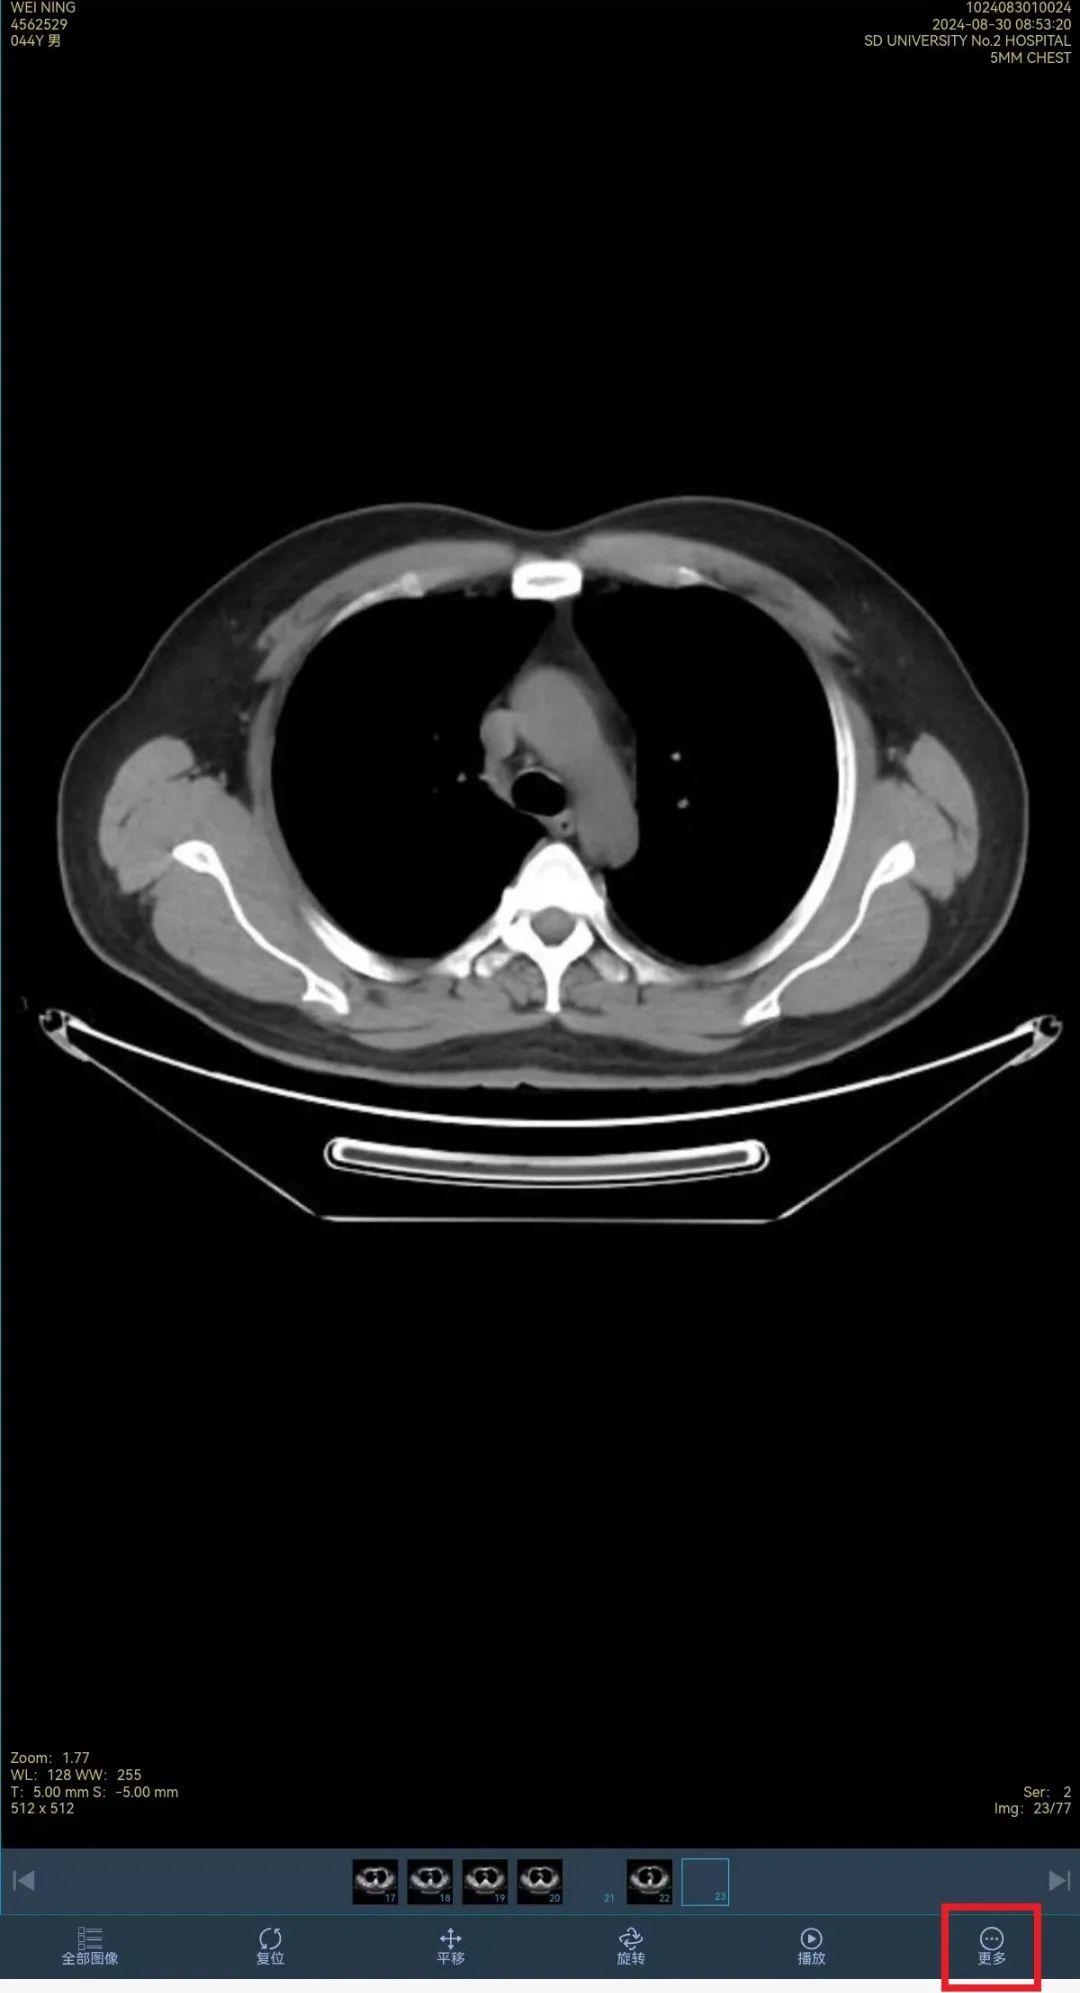

“云胶片”是一种数字化的医学影像,通过将医学影像系统生成的无损DICOM图像上传至云端进行存储和管理。近年来,山东大学第二医院积极响应《山东省推进 “互联网 + 医疗健康” 示范省建设行动计划》,优化医疗服务流程,上线基于省全民健康信息平台的医疗机构数字影像的“云胶片”服务,通过云端平台即可访问和查看自己的影像数据,同时可分享给医生进行查阅,使就医过程更加便捷。

7.点击右下角“更多”

8.选择“分享时效”

9.点击“复制链接”,将链接粘贴分享给他人